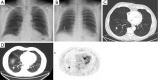

Figure 1

Digital chest tomosynthesis image showing a solid pulmonary nodule in a 57-year-old woman. (A) The pulmonary nodule is not visible on the postero-anterior chest radiograph; (B) digital chest tomosynthesis showing a left nodule (white arrow), confirmed in the CT scan; (C) the pathological examination, after the VATS lobectomy, showed the presence of an adenocarcinoma.